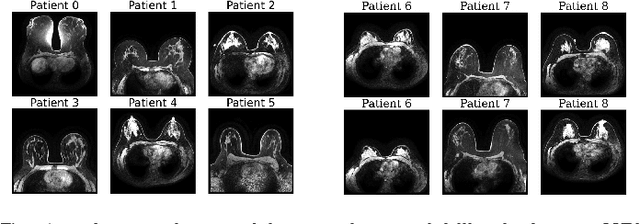

Abstract:Modern medical image translation methods use generative models for tasks such as the conversion of CT images to MRI. Evaluating these methods typically relies on some chosen downstream task in the target domain, such as segmentation. On the other hand, task-agnostic metrics are attractive, such as the network feature-based perceptual metrics (e.g., FID) that are common to image translation in general computer vision. In this paper, we investigate evaluation metrics for medical image translation on two medical image translation tasks (GE breast MRI to Siemens breast MRI and lumbar spine MRI to CT), tested on various state-of-the-art translation methods. We show that perceptual metrics do not generally correlate with segmentation metrics due to them extending poorly to the anatomical constraints of this sub-field, with FID being especially inconsistent. However, we find that the lesser-used pixel-level SWD metric may be useful for subtle intra-modality translation. Our results demonstrate the need for further research into helpful metrics for medical image translation.